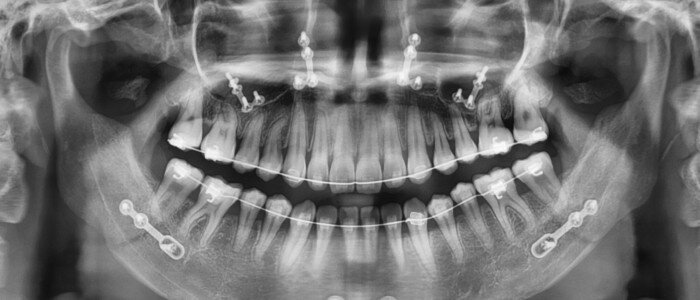

Teeth 1

Dental Imaging X-Ray's

View attachment 4444397